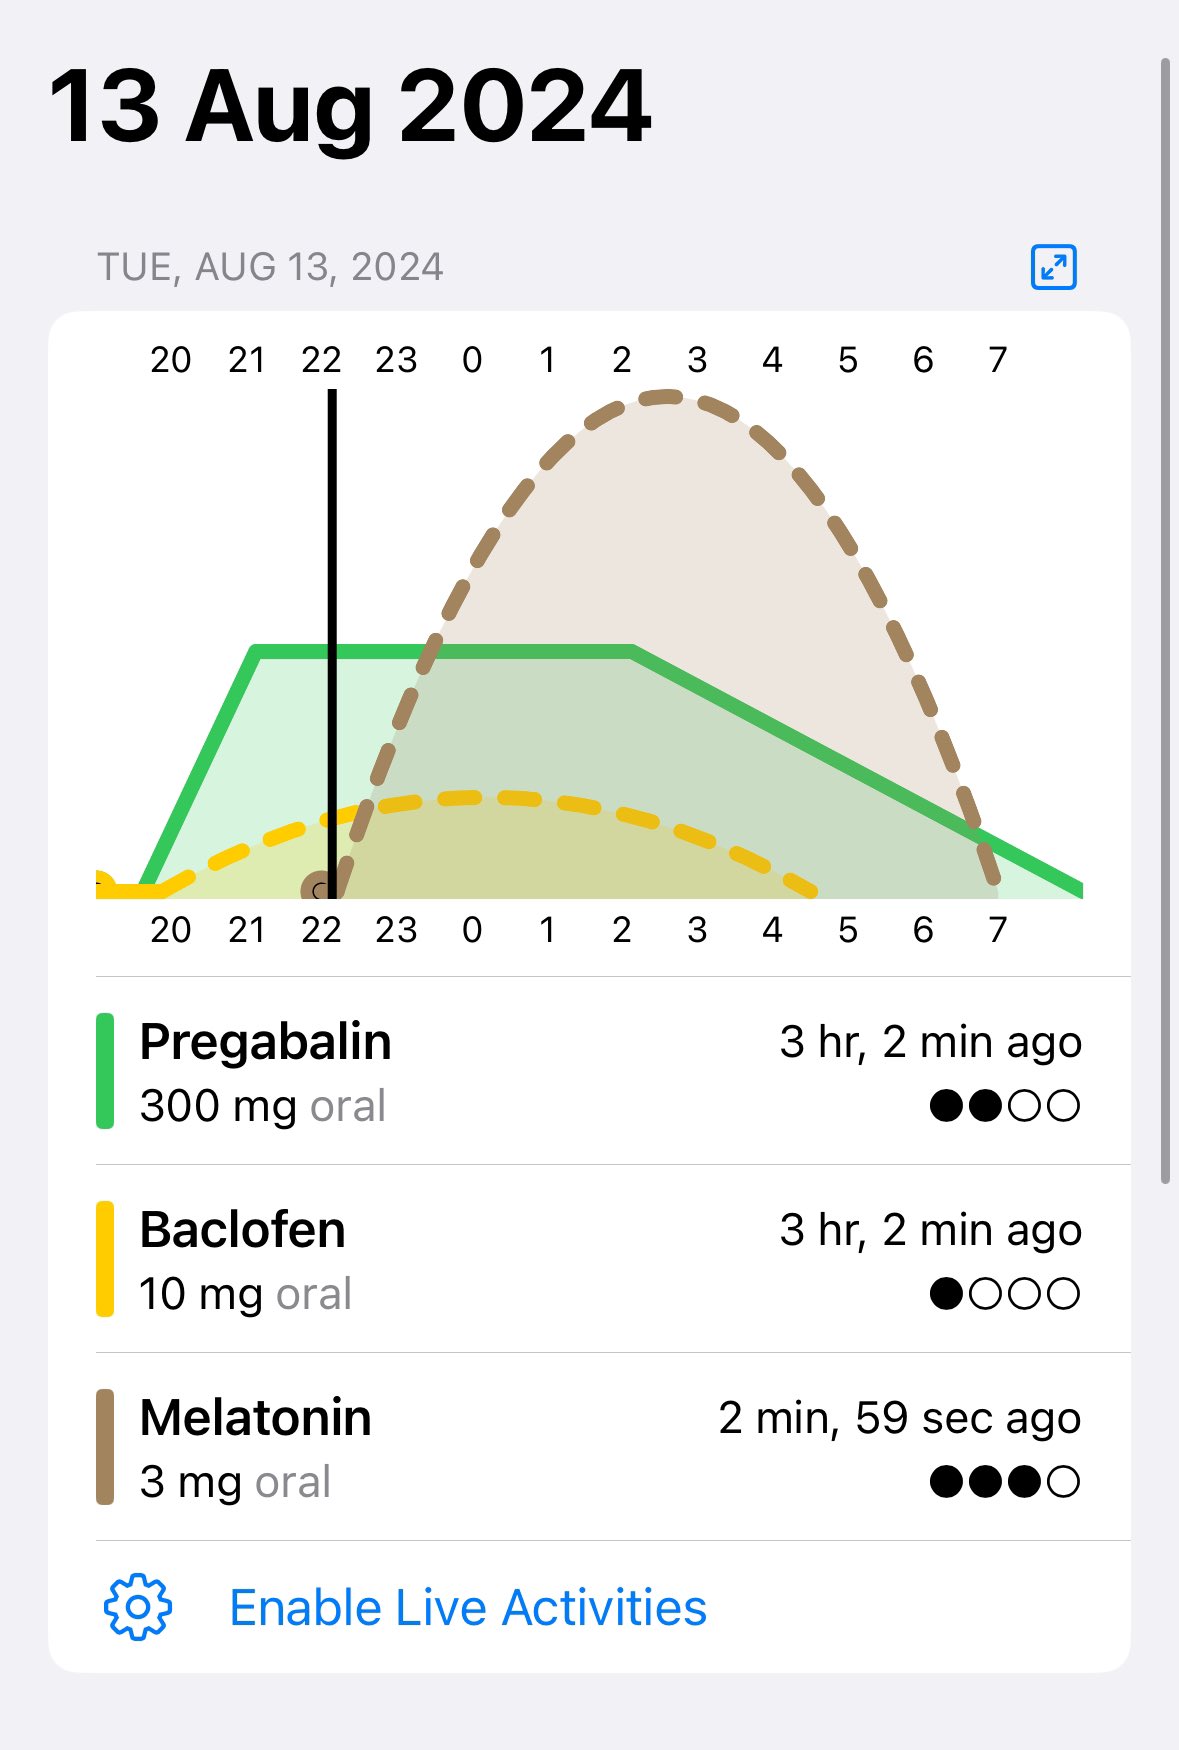

2024-08-14 11:34:53 UTC

甚至在第二天有余晖的感觉,虽然发生了很多破事但没怎么影响心情*抗焦虑&镇静

运动协调性稍差,表现为走路和站立时平衡不好

此剂量下对睡眠的改善作用,增加了慢波睡眠且没有影响rem,精力恢复+

FDA数据,在临床剂量下(75-600mg)普瑞巴林的依赖性低于bzd,并相比之下它产生的认知和精神运动障碍较轻 https://t.co/TJ7ZOQ7pbC